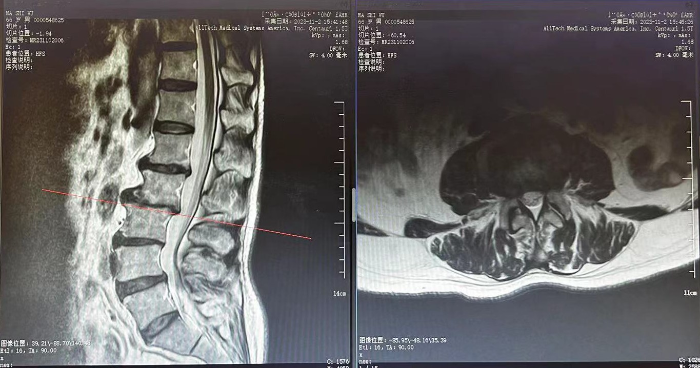

馬師(shī)傅以間斷性腰背部疼痛3月餘、加重2天爲主訴入院,王康醫生(shēng)查體(tǐ)後,結合腰椎MRI(核磁共振成像),考慮爲腰椎間盤突出伴神經根痛、腰椎椎體(tǐ)滑脫,決定給予小針刀松解神經卡壓治療。